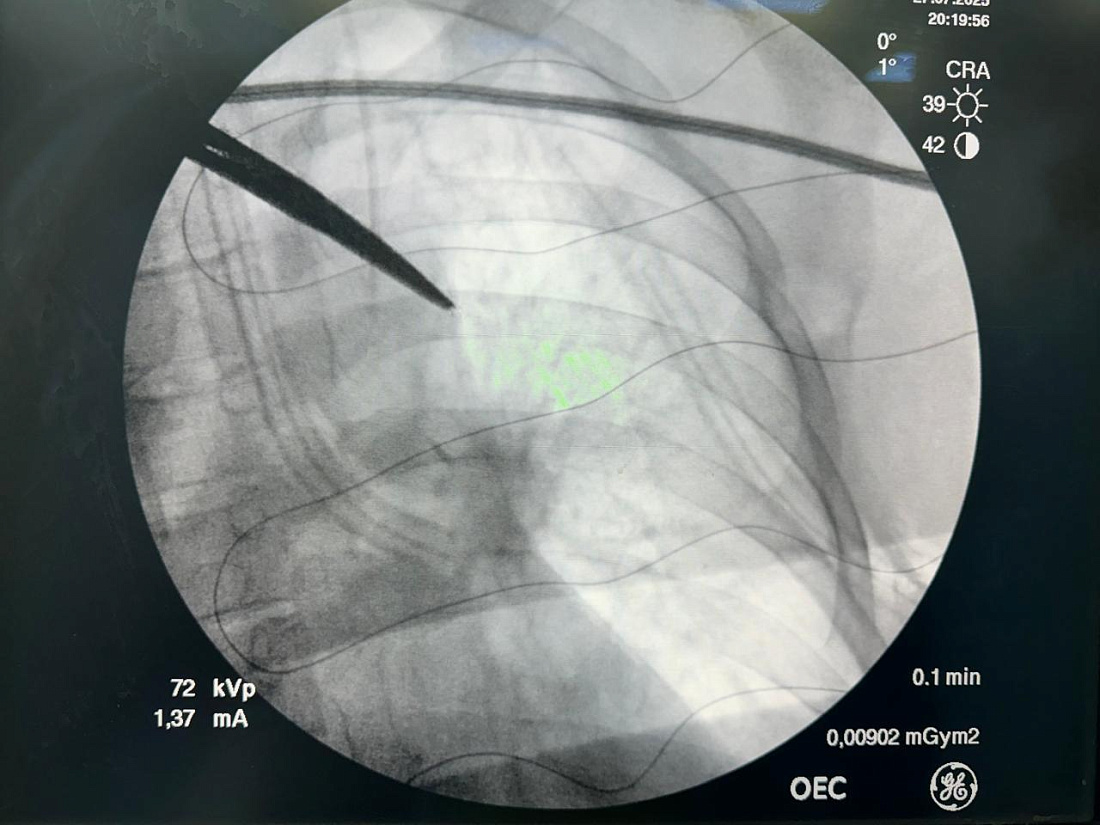

Хирурги столкнулись с чрезвычайно сложной задачей: металлический осколок размером более 10 мм находился буквально в миллиметре от главной артерии легкого. Обычно в таких случаях делают большой разрез грудной клетки, но московские специалисты смогли провести операцию через небольшие проколы с помощью эндоскопического оборудования. Всем процессом в операционной руководил генеральный директор НМИЦ хирургии им. А.В. Вишневского академик РАН Амиран Ревишвили.

Фотографии с официального сайта НМИЦ хирургии им. А.В. Вишневского